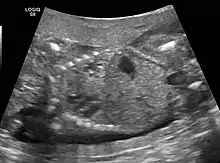

CPAMs are often identified during routine prenatal ultrasonography. Identifying characteristics on the sonogram include: an echogenic (bright) mass appearing in the chest of the fetus, displacement of the heart from its normal position, a flat or everted (pushed downward) diaphragm, or the absence of visible lung tissue.

The earliest point at which a CPAM can be detected is by prenatal ultrasound. The classic description is of an echogenic lung mass that gradually disappears over subsequent ultrasounds. The disappearance is due to the malformation becoming filled with fluid over the course of the gestation, allowing the ultrasound waves to penetrate it more easily and rendering it invisible on sonographic imaging. When a CPAM is rapidly growing, either solid or with a dominant cyst, they have a higher incidence of developing venous outflow obstruction, cardiac failure and ultimately hydrops fetalis. If hydrops is not present, the fetus has a 95% chance of survival. When hydrops is present, risk of fetal demise is much greater without in utero surgery to correct the pathophysiology. The greatest period of growth is during the end of the second trimester, between 20–26 weeks.

A measure of mass volume divided by head circumference, termed cystic adenomatoid malformation volume ratio (CVR) has been developed to predict the risk of hydrops. The lung mass volume is determined using the formula (length × width × anteroposterior diameter ÷ 2), divided by head circumference. With a CVR greater than 1.6 being considered high risk. Fetuses with a CVR less than 1.6 and without a dominant cyst have less than a 3% risk of hydrops. After delivery, if the patient is symptomatic, resection is mandated. If the infant is asymptomatic, the need for resection is a subject of debate, though it is usually recommended. Development of recurrent infections, rhabdomyosarcoma, adenocarcinomas in situ within the lung malformation have been reported.[4]